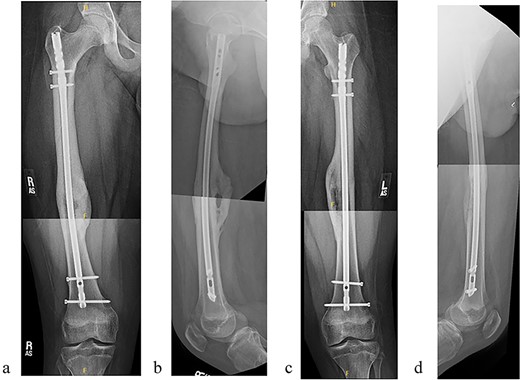

A 14-year-old boy sustained closed right and left mid-shaft femur fractures (Right OTA 32-A3, Left OTA 32-B2) after an all-terrain vehicle accident (Fig. 1a and b). The patient was classified as obese with a BMI of 37. Bone age was determined to be approaching skeletal maturity and so a rigid trochanteric entry femoral rod was selected for the implant [15, 16] (Fig. 2). Laboratory derangement included hyperphosphatemia and hypoalbuminemia. Therefore, additional measures to include early fracture stabilization and the RIA adjunct was selected for our patient [17].

(a) Right femur fracture (OTA 32-A3). (b) Left femur fracture (OTA 32-B2).